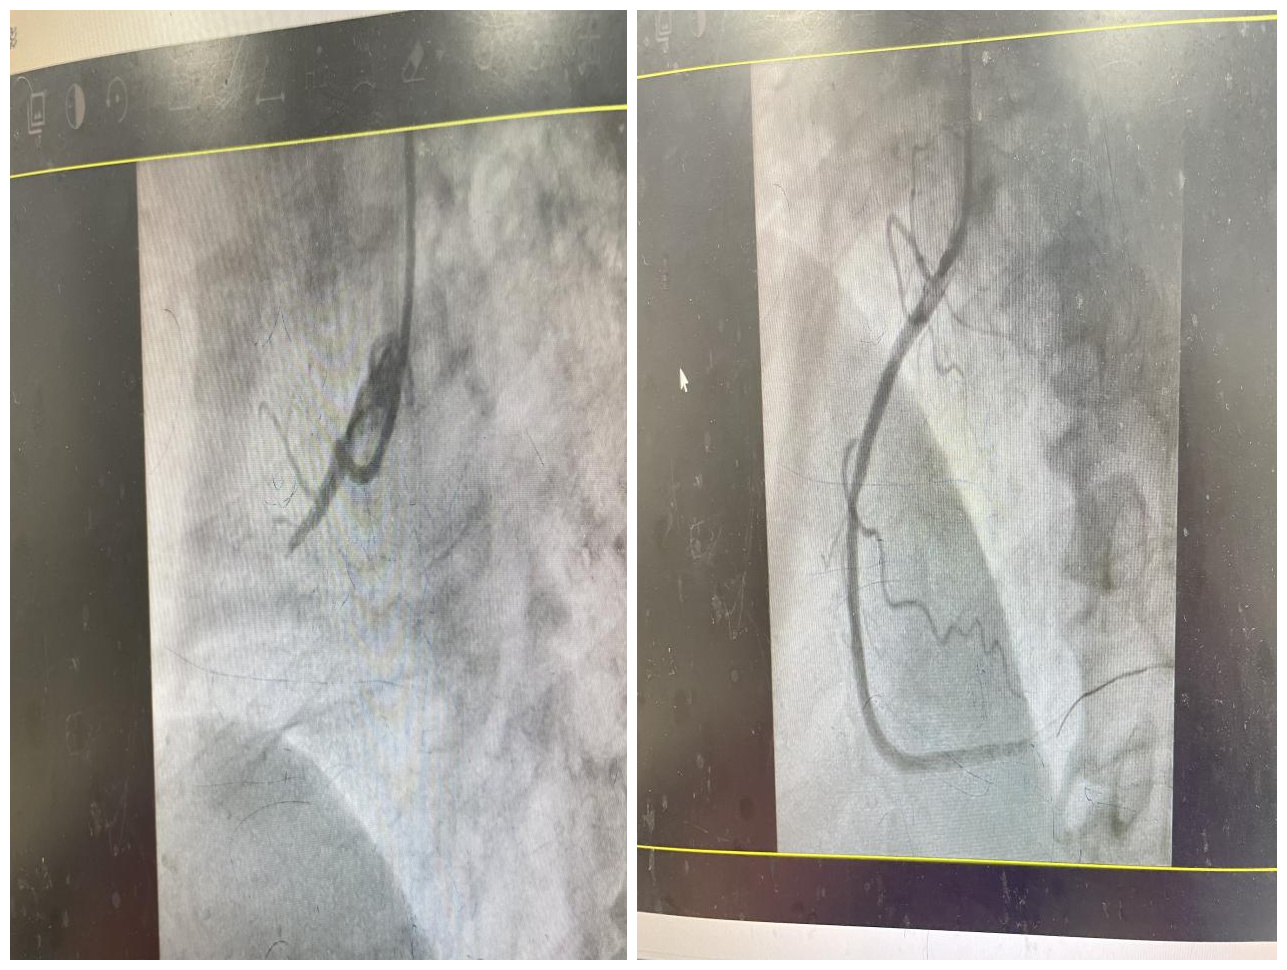

近日,我院心血管内科成功抢救一名急性ST段抬高型下壁心肌梗塞心源性休克患者,成功挽救了患者的生命。

开展特色诊疗项目:冠心病介入诊疗:急性心肌梗死、复杂冠脉病变治疗(血管内血栓抽吸术、冠脉内斑块旋磨术及血管内超声检查术);心律失常的介入诊疗:射频消融手术、单腔、双腔起搏器植入术;先天性心脏病的介入诊疗:房缺经皮导管介入封堵术等。外周血管的治疗:腹主动脉瘤的介入治疗,下腔静脉滤器的置入和取出术等。